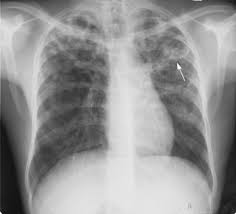

Tuberkulosis (TB) adalah penyakit menular yang disebabkan oleh Mycobacterium tuberculosis (Mtb) yang terutama menyerang paru-paru (TB paru). Pengobatannya meliputi empat obat anti-TB lini pertama selama 6 bulan yaitu isoniazid (INH), rifampisin (RIF), etambutol (ETH), dan pirazinamid (PZA). Namun, efektivitas ini terbatas karena perlindungan bakteri Mtb pada lesi paru. Pendekatan alternatif melibatkan pemberian obat langsung ke paru-paru melalui inhalasi menggunakan metode mikrosfer inovatif, yang dapat meningkatkan kemanjuran pengobatan.